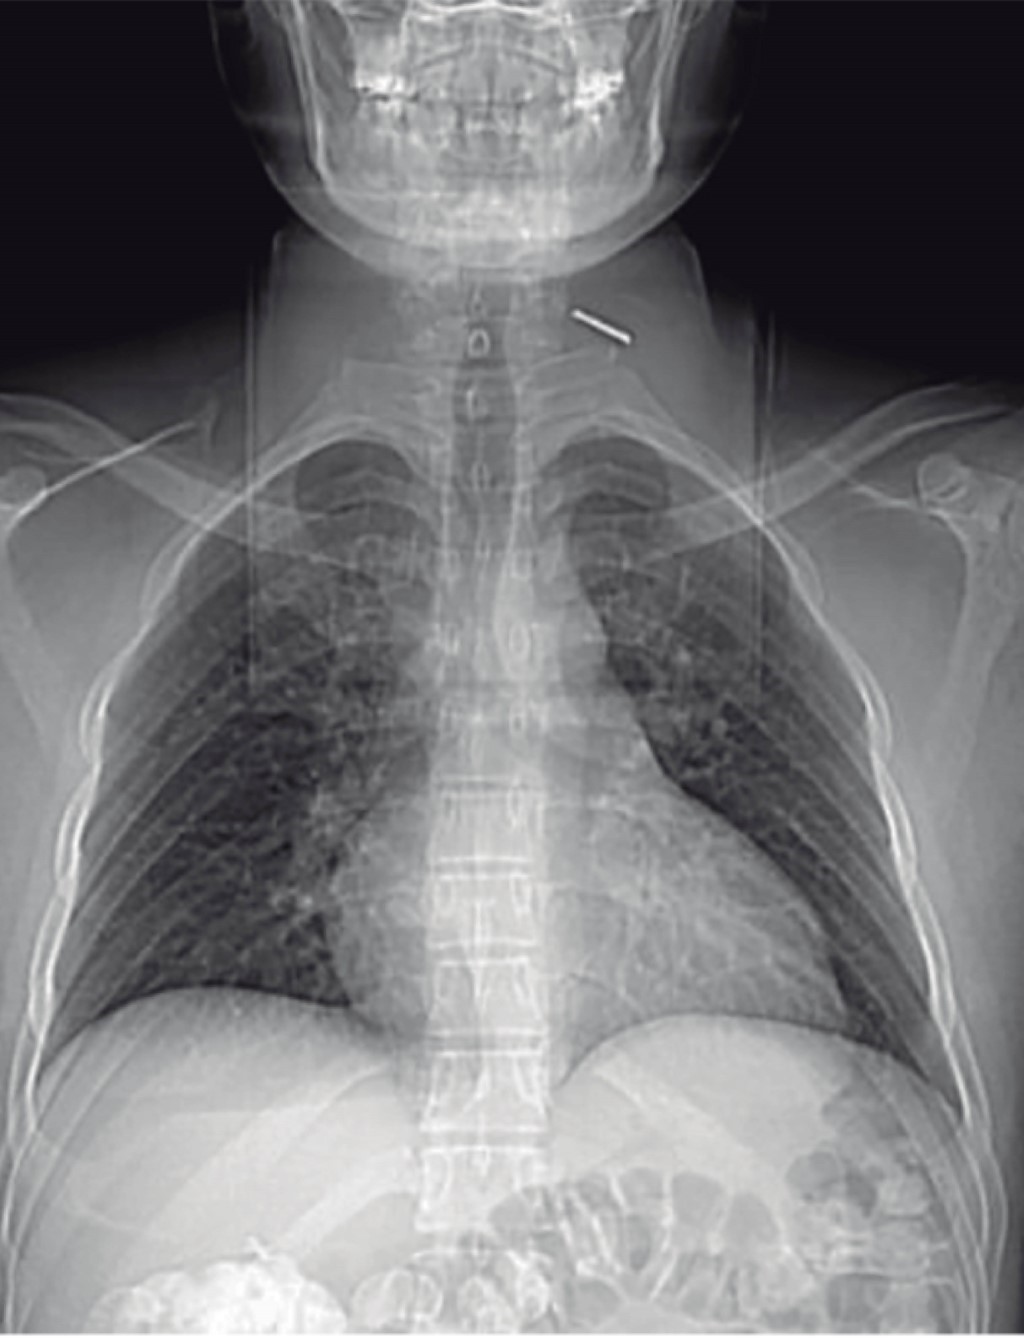

En radiografía anteroposterior (AP) de hombro derecho y radiografía anteroposterior de columna cervical se evidencia clavo Kirschner migrado a nivel del segmento C7-T1 (Figuras 1 y 2). En imágenes tomográficas se evidencia cuerpo extraño a nivel foraminal derecho (Figura 3).

Paciente masculino de 43 años de edad quien, cinco meses previos a la atención hospitalaria, presenta cervicalgia moderada sin sintomatología acompañante sin recibir atención médica. Siete días previos a la valoración y posterior a trauma contuso en región cervical y dorsal, presenta dolor intenso en región cervical, además de pérdida súbita de sensibilidad y fuerza motriz en cuatro extremidades. El paciente tiene como antecedente osteosíntesis de clavícula derecha con placas de reconstrucción y clavo Kirschner en institución privada hace ocho años. Al momento de la valoración actualmente reportada, se presenta movilizado en silla de ruedas, con tetraparesia, nivel neurológico C6, ASIA B. Se revisan radiografías anteroposterior y lateral de columna cervical en las que se evidencia clavo Kirschner en segmento C7-T1 (Figura 10). En tomografía computarizada se constata invasión de cuerpo extraño a conducto medular (Figura 11). Se realiza extracción quirúrgica de clavo Kirschner mediante abordaje supraclavicular derecho (utilizado para exploración de plexo braquial), se realiza disección neurovascular; se logra identificación directa de punta de clavo K mediante intensificador de imágenes. Se retira el clavo sin dificultad, no presentó fuga de líquido cefalorraquídeo (Figura 12A y B). El paciente en postoperatorio inmediato y a los 45 días posteriores a la cirugía no presenta cambios en estado neurológico.